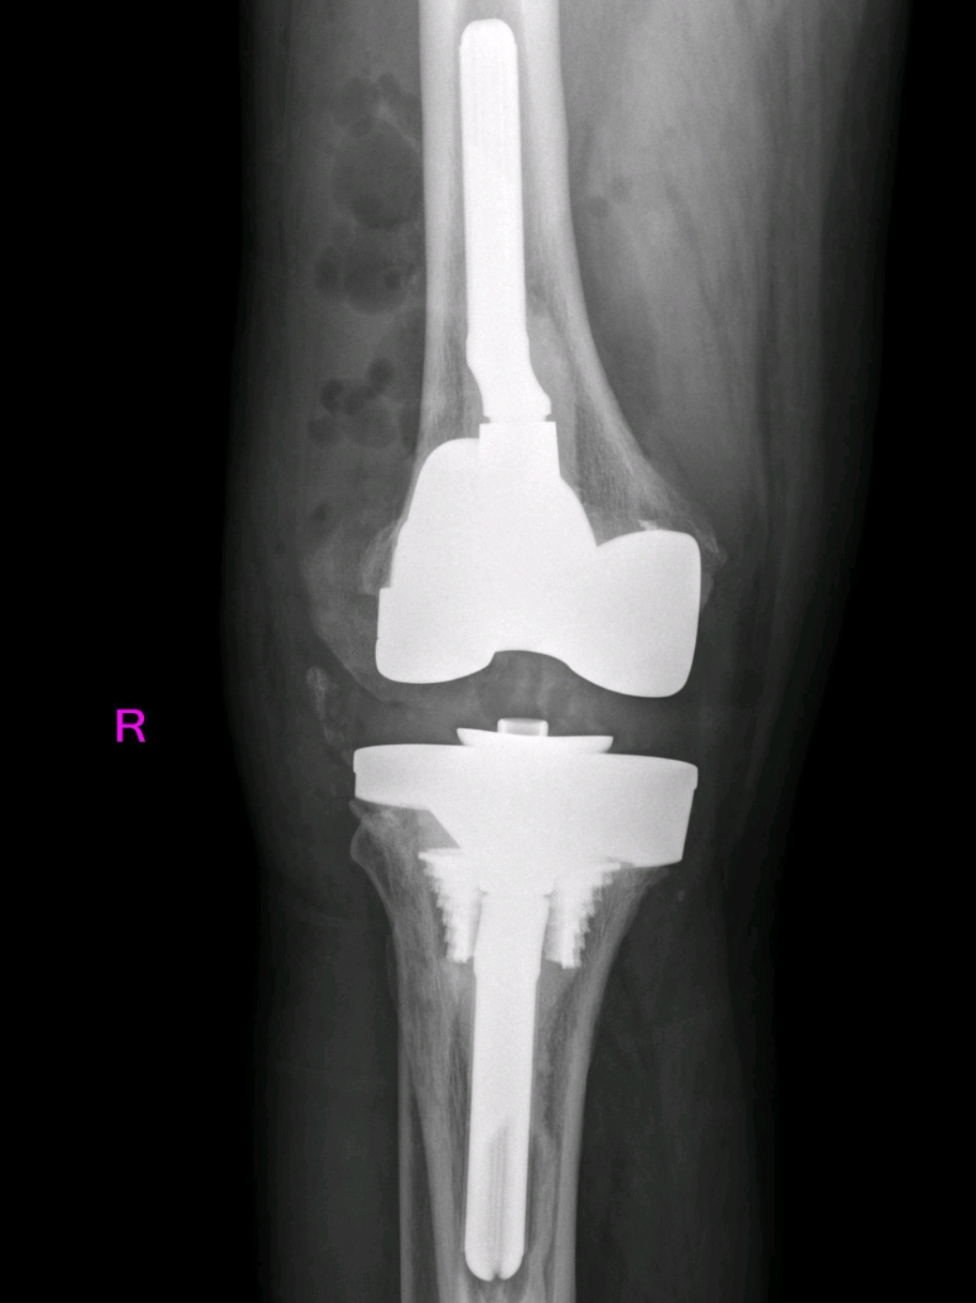

与初次关节置换相比,翻修术对手术医生、患者都具有挑战性。潘永德迅速组织了会诊,经过多次深入讨论,最终为陈大叔量身定制了一套详细的手术方案。在清华长庚医院陈连旭教授的指导下,历经6个小时,关节外科团队成功为患者行“右侧全膝关节假体翻修术”。

全膝关节假体翻修术后

术后,陈大叔在医护人员的精心照料下,逐渐恢复了健康。医生们定期为他进行康复指导,帮助他进行膝关节的功能锻炼。同时,他们还对陈大叔进行了全面的检查,确认他的膝关节没有出现感染、假体移位等并发症,这让他和家人都感到无比的欣喜和感激。